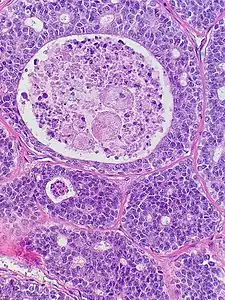

![]() | |

| Micrograph of an adenoid cystic carcinoma of a salivary gland (right of image): Normal serous glands, typical of the parotid gland, are also seen (left of image), H&E stain. | |